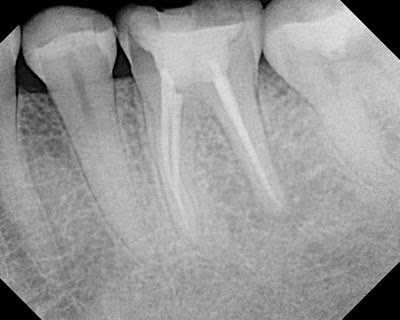

The radiographic history would indicate that the endodontic retreatment performed in 2006 was was successful with healing of distal lesion.